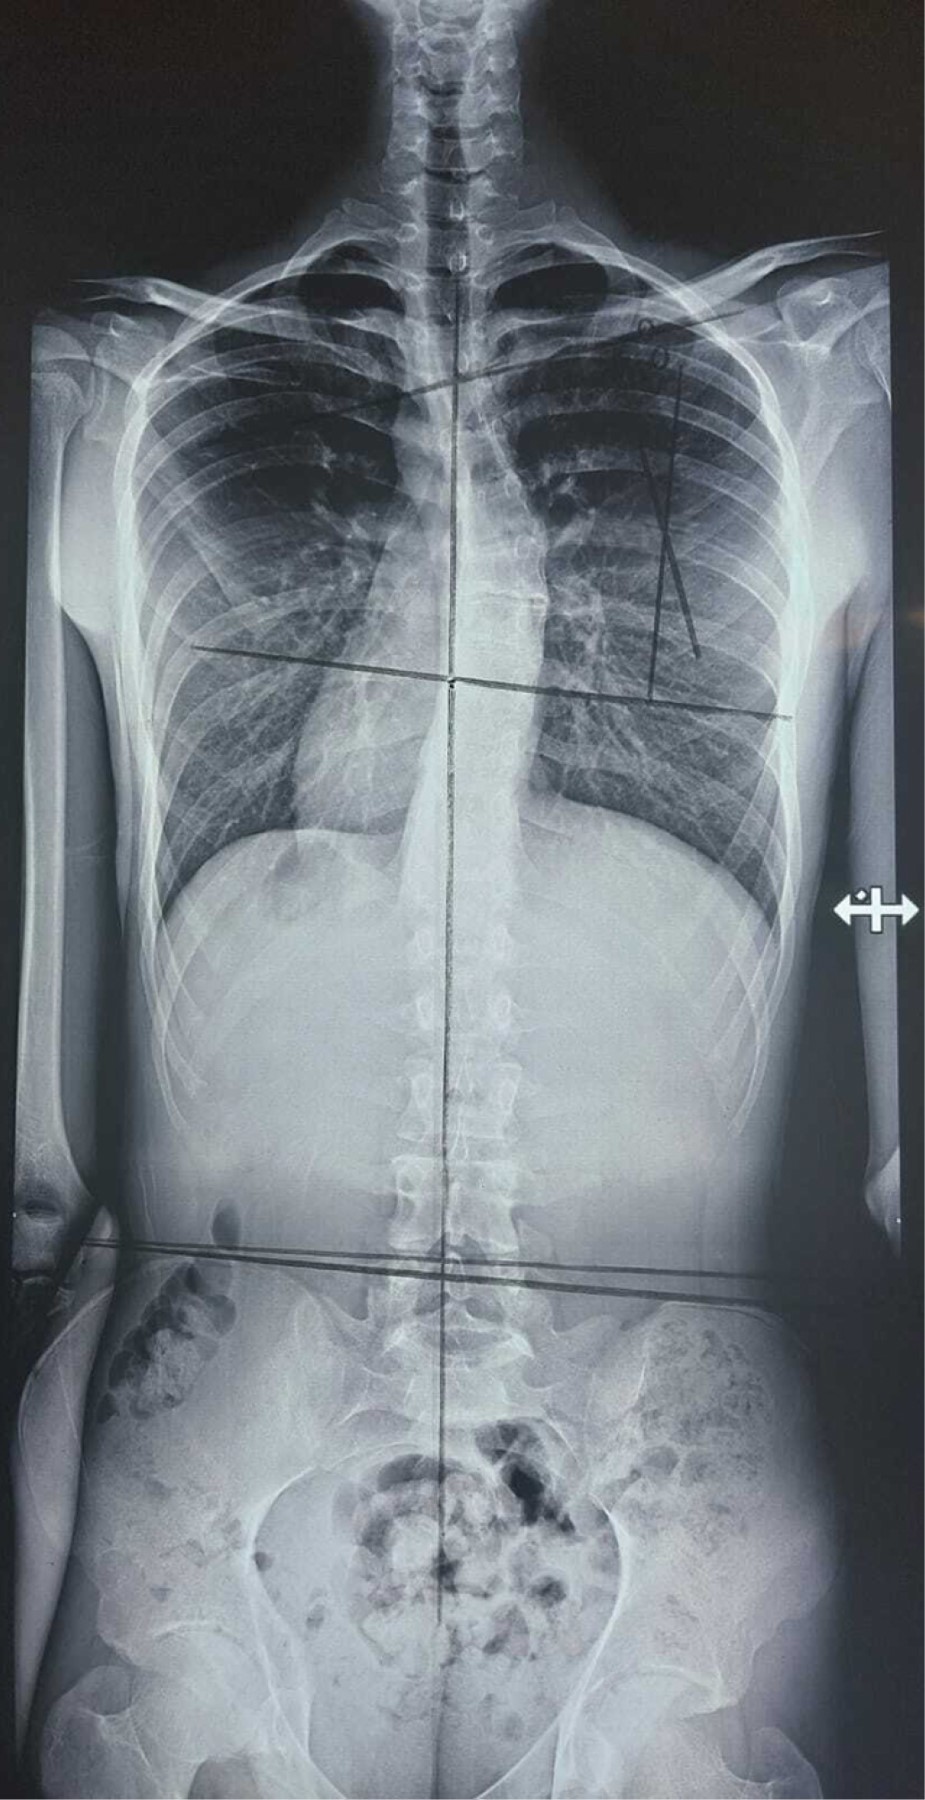

Se presenta caso de paciente masculino de 22 años de edad, el cual es diagnosticado con enfermedad de Scheuermann con una curva torácica de 105°, el paciente muestra madurez esquelética completa, por lo que se propone tratamiento quirúrgico. Esta enfermedad es una patología de constante afrontamiento para el cirujano de columna, por lo que es importante realizar un rápido repaso de la misma y de nuestro accionar como médicos.INTRODUCCIóN

Paciente masculino de 22 años de edad y sin antecedentes de relevancia, el cual se presenta a consulta por deformidad, la cual le crea inseguridad estética y dolor recurrente de región torácica. Se solicitan radiografías anteroposterior (AP) y lateral panorámicas de columna, se detecta una deformidad de 105° de cifosis torácica (Figuras 1 y 2). Se propone al paciente realización de instrumentación posterior y fusión con corrección de curva torácica, quien acepta el tratamiento. Se realiza cirugía de instrumentación y fusión posterior exclusiva de T2 a L2 con tornillos poliaxiales mediante neuronavegación con O-ARM™ y neuromonitoreo (Figuras 3, 4 y 5). El paciente muestra buena evolución inmediata con una pérdida sanguínea menor de 200 ml durante las tres horas de procedimiento quirúrgico, además de buena evolución durante el primer, tercer y sexto mes con desaparición del dolor y corrección de curva a 40°(Figuras 6 y 7).